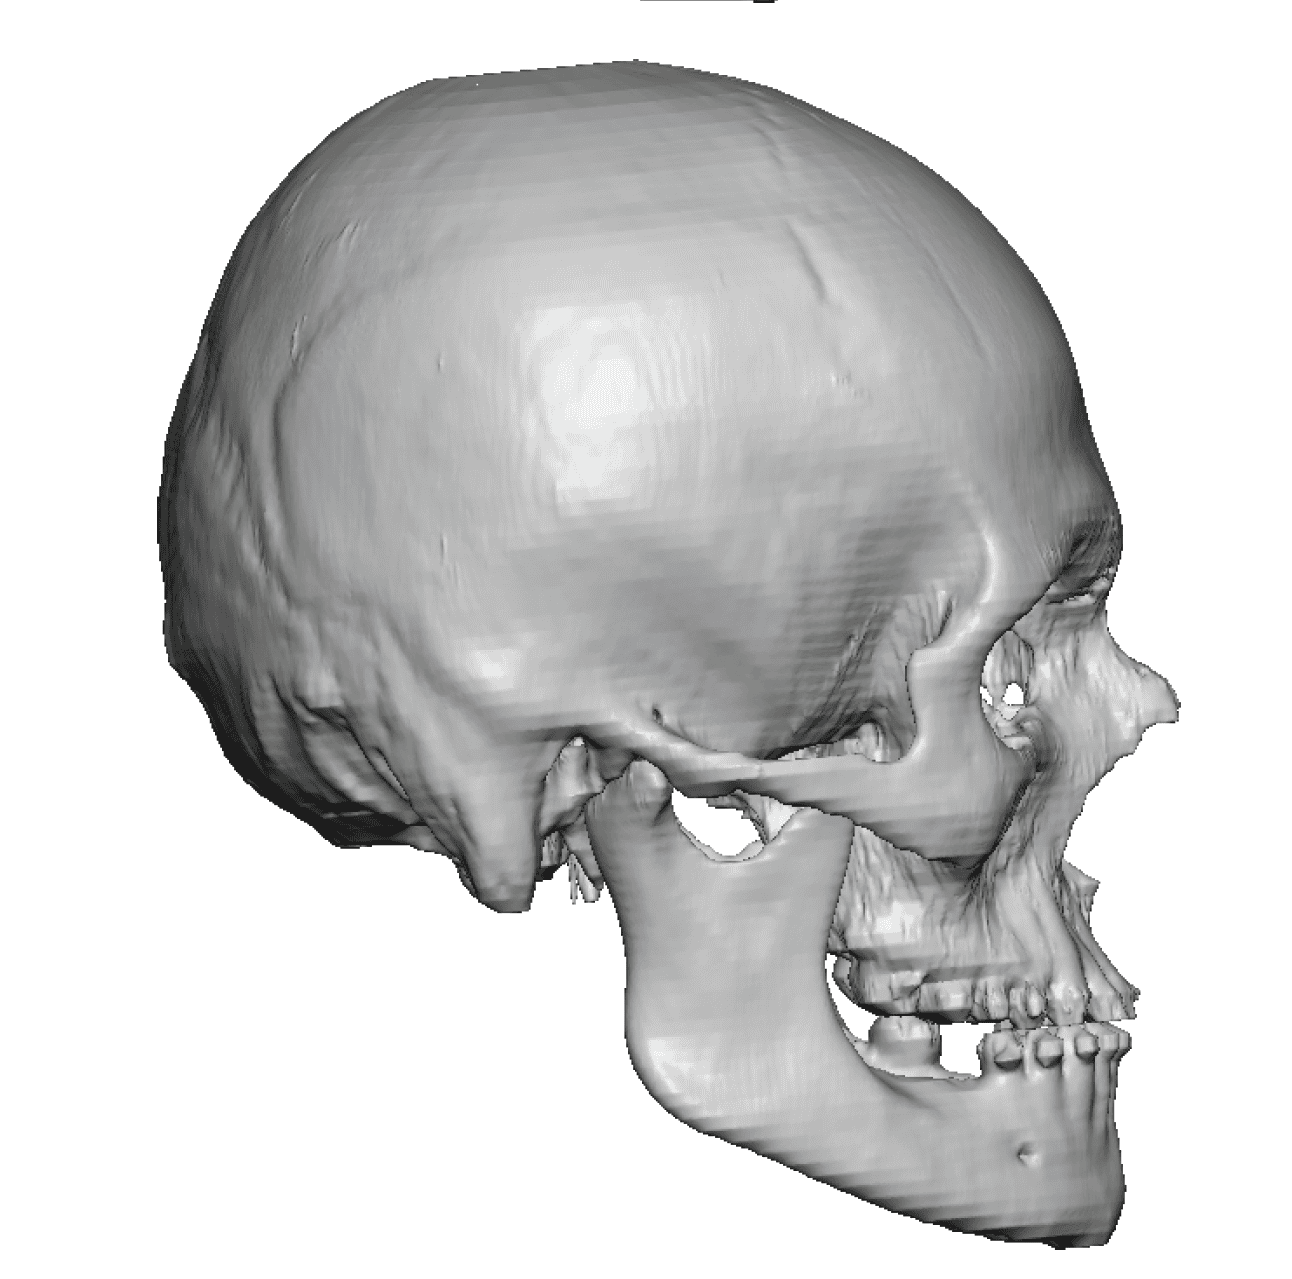

Patient 49

Desire for further skull augmentation after a primary skull implant.

Five years after an initial custom skull implant placement a new custom skull implant that increased the volume by 35% was placed.

Desire for further skull augmentation after a primary skull implant.

Five years after an initial custom skull implant placement a new custom skull implant that increased the volume by 35% was placed.